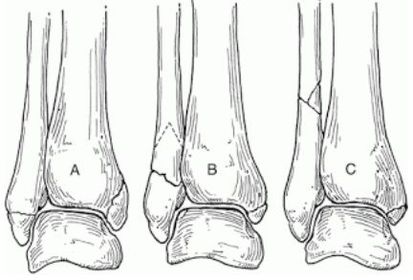

What classification system is this? Describe the 3 classifications | Weber Ankle Fracture Classification A = Fracture below syndesmosis B = Fracture begins at joint level & extends proximally in an oblique fashion C = Fracture above the joint line |